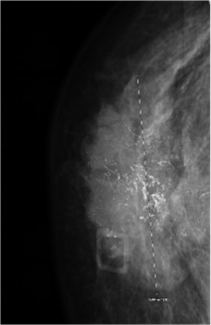

Case highlights breast cancer screening considerations in transgender women with long-term hormone therapy and familial risk factors.